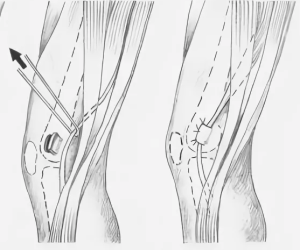

Эндоваскулярное вмешательство выполнить не представлялось возможным. 08.10.2024 осуществлена резекция подколенной артерии, аутовенозное протезирование. В положении пациента на животе Z-образным разрезом выполнен доступ к ПА. Выделена ложная аневризма (рис. 2). Приводящий к аневризме и отводящий сегменты артерии и вены выделены. Аневризматическая чаша раскрыта, удалены тромботические массы (рис. 3). Приготовлен графт из большой подкожной вены контралатеральной конечности, реверсирован, проведена гидропрессия. ПА протезирована аутовеной (рис. 4). Восстановлен кровоток. Ревизия седалищного нерва показала, что повреждений нет. Выполнено послойное ушивание операционных доступов.

Послеоперационный период протекал без осложнений. Пациент был переведен в Иркутский научный центр хирургии и травматологии. 02.12.2024 задним доступом 15 см обнажена зона перелома заднего края медиального мыщелка бедренной кости. Осколок выделен из рубцов, удален при помощи распатора (рис. 5).